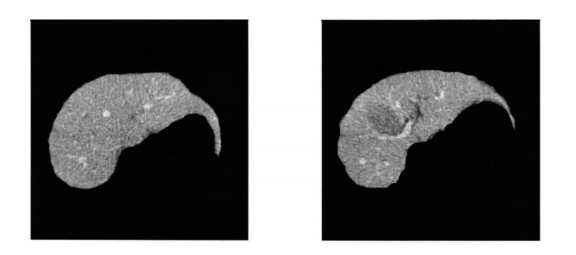

Figure 4.  Schematic diagrams of the internal liver tube

Figure 8.  Three-dimensional reconstruction of hepatic veins

Figure 9.  Three-dimensional smoothing effect diagrams